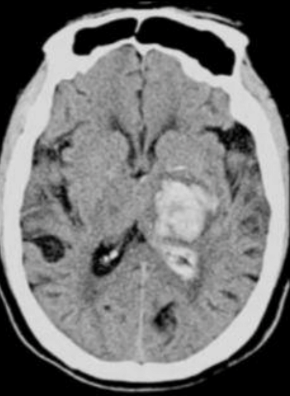

¿Qué es?¿Porqué’

EVC hemorrágico - se ve la sangre hiperdensa y se encuentra en los ganglios basales